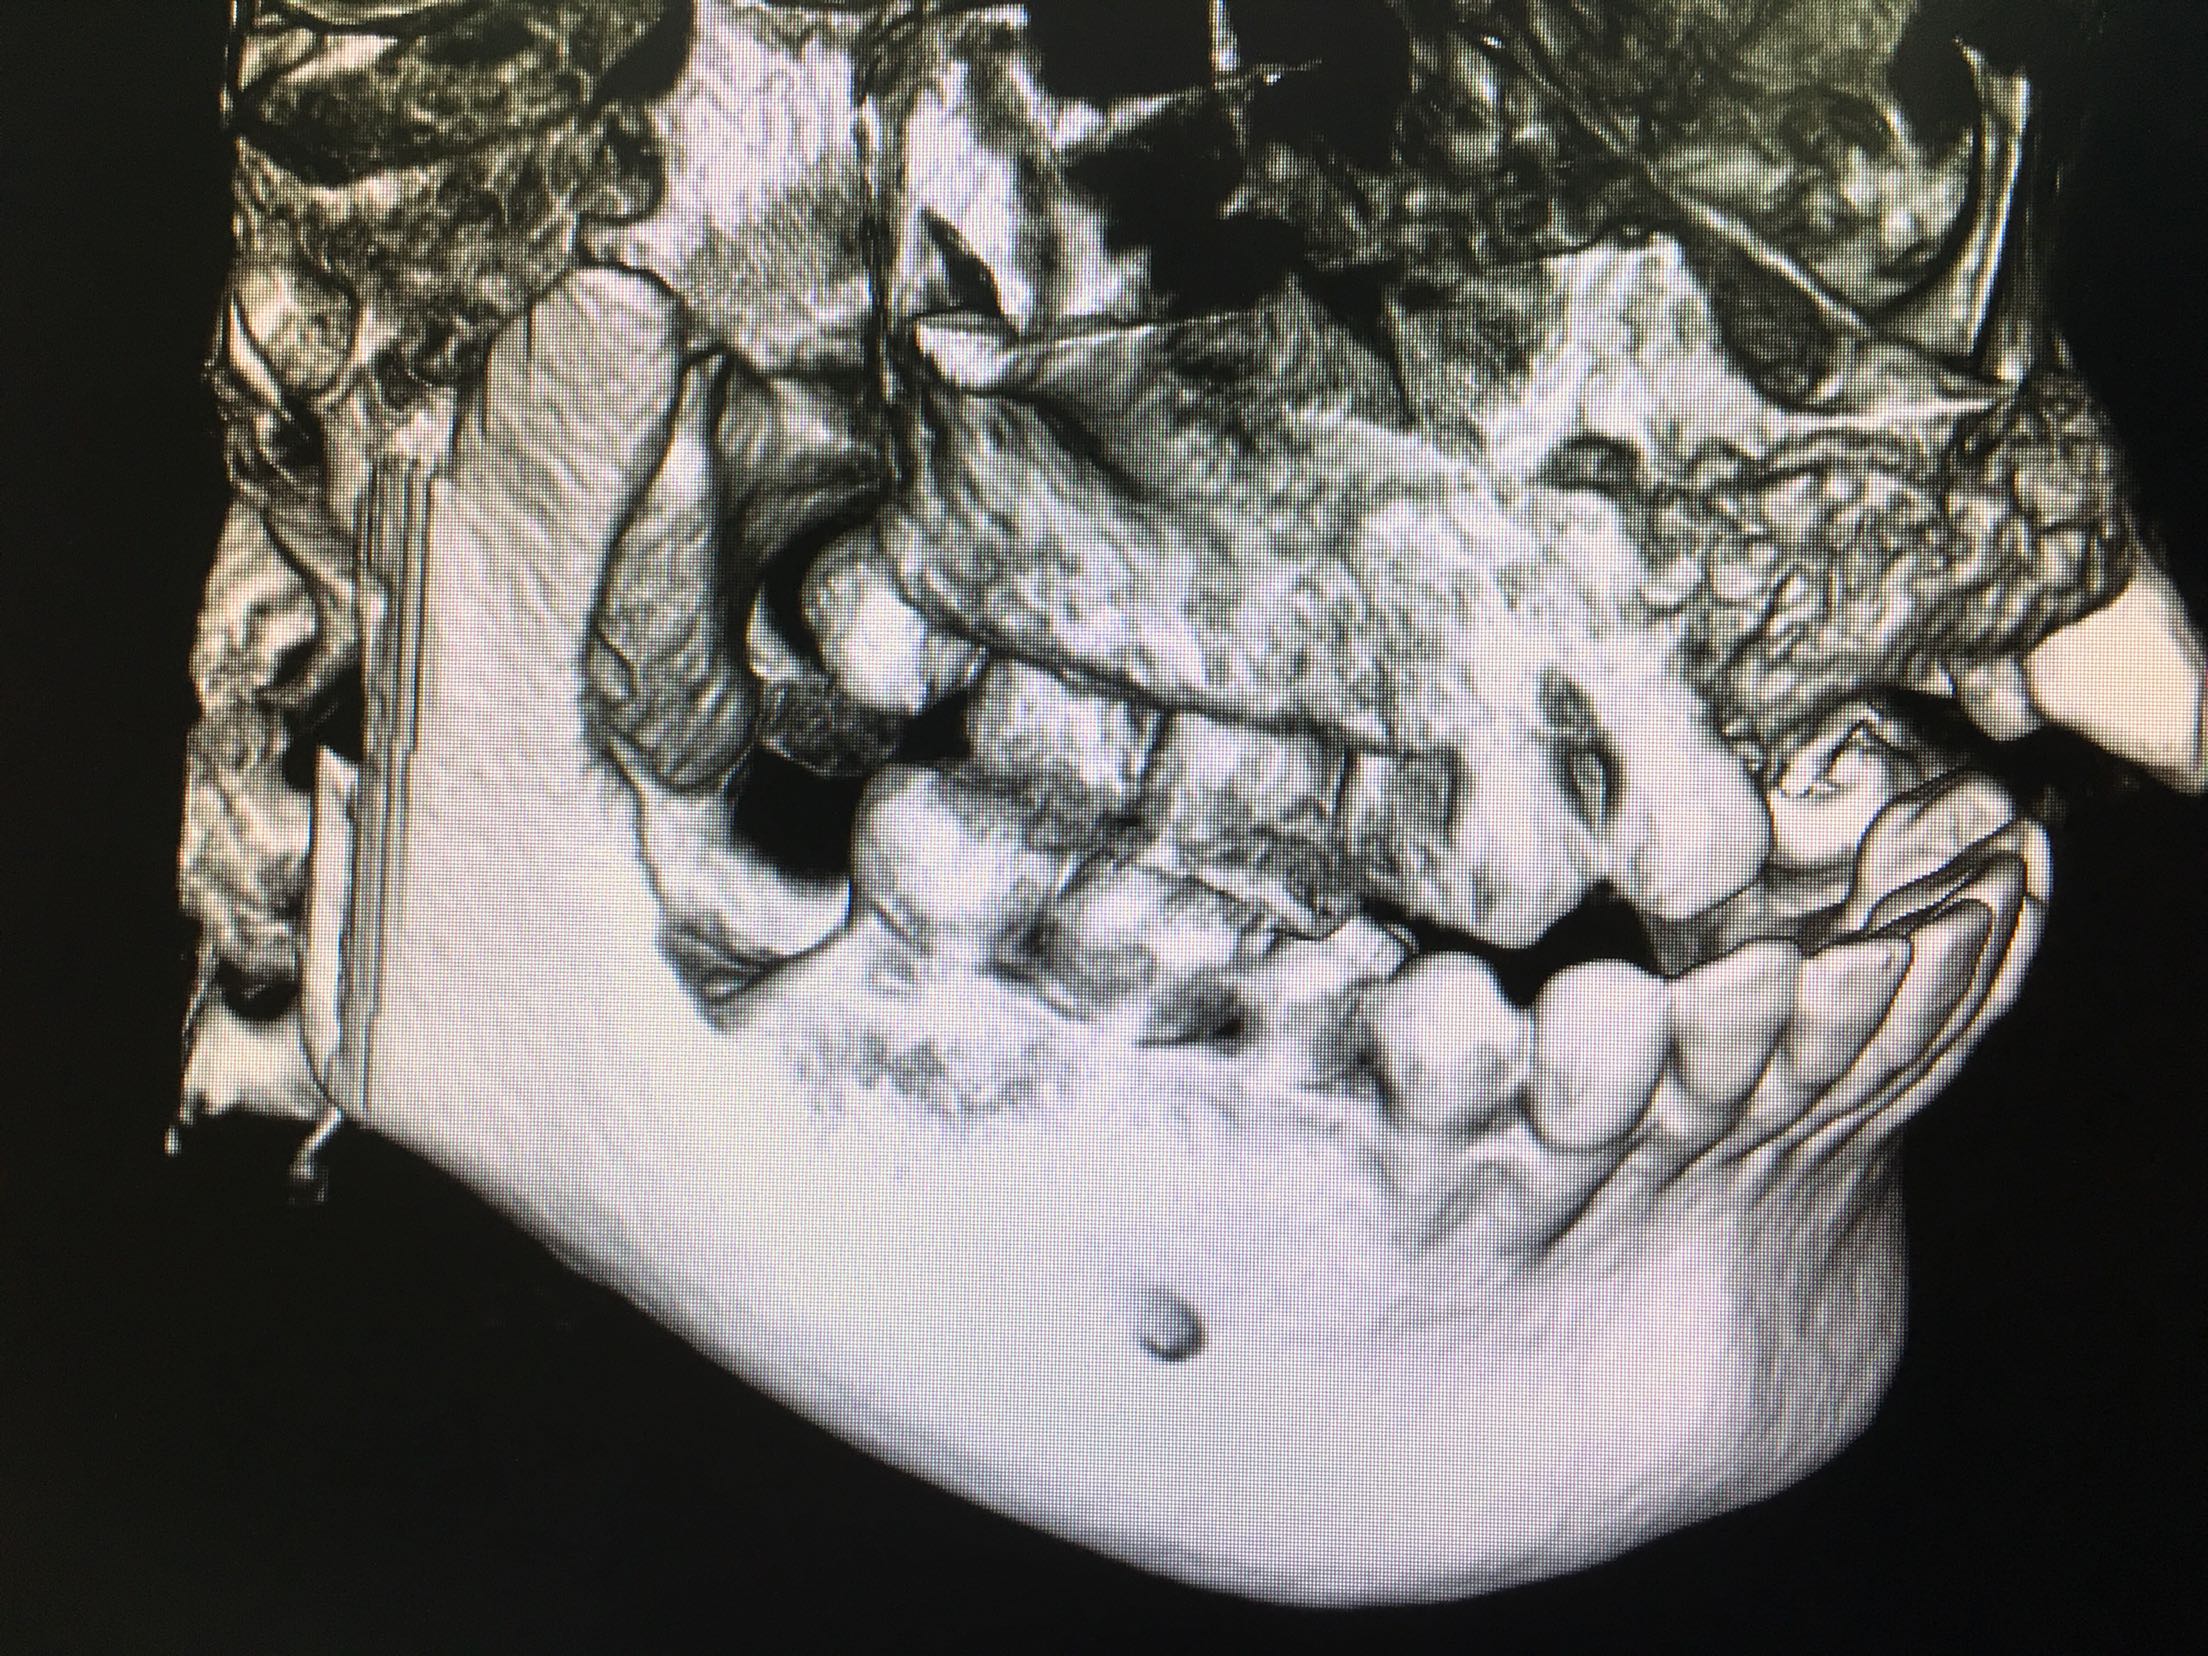

CBCT示11、12、21、22牙缺失,牙槽骨呈刀刃状,38、48牙阻生。

38、48牙超刀拔除,取双侧骨块,11、12、21、22梯形切口切开、翻瓣,切断粘骨膜松弛,骨块钛钉固定唇侧,植入Bio-ss骨粉0.5g,覆盖生物膜,严密缝合!嘱半年后种植!